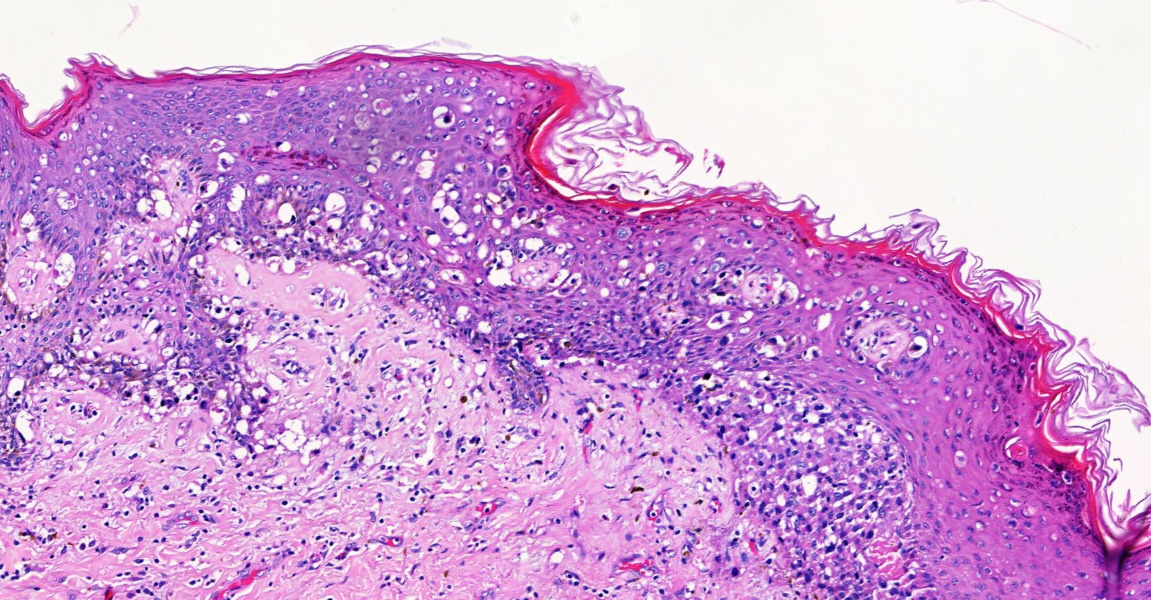

Histological section shows invasive Paget's disease with dermal Paget Disease With Dermal Invasion A ≥50% reduction in empd lesion size was achieved in 100% and 75.3% of patients treated with surgery and topical therapies, respectively. Mammary paget disease with dermal invasion (invmpd) is rare, and its prognosis remains largely unknown. Invasive mammary paget's disease (mpd) is an extremely rare eczematous eruption on the nipple and areola with an invasion of the dermis by.. Paget Disease With Dermal Invasion.